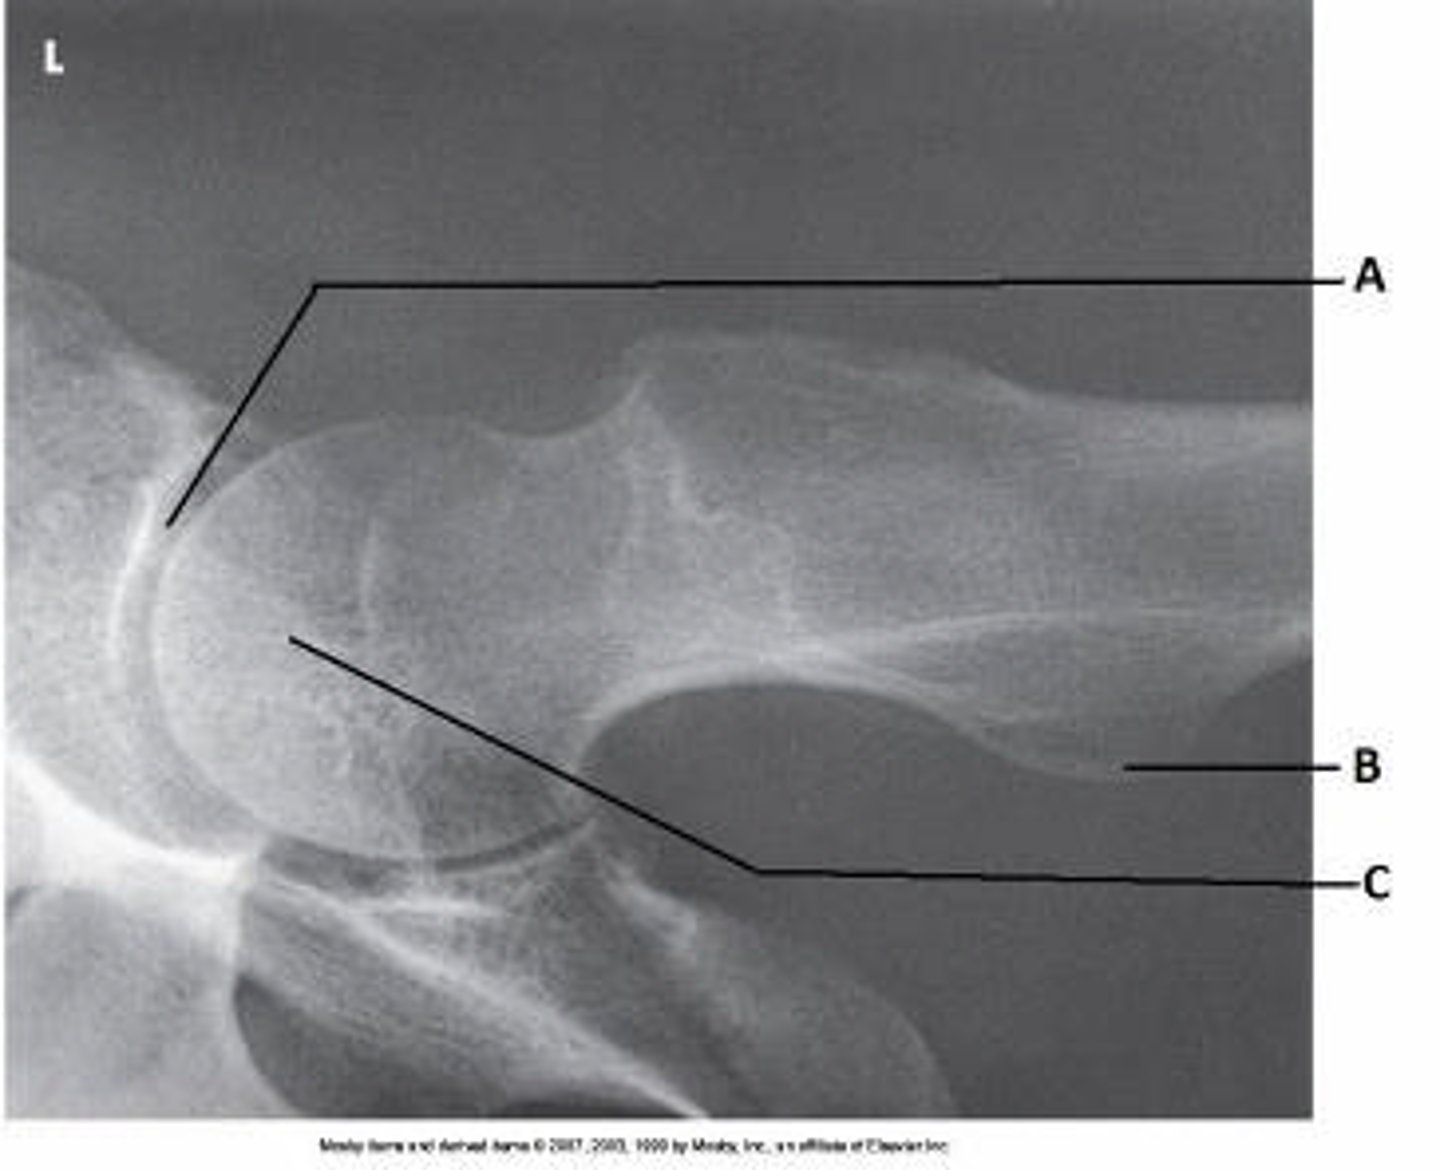

Acetabulum

What anatomy is labeled as letter A in the image below?

Femoral head

Femoral neck

Greater trochanter

Lesser trochanter

What anatomy is labeled as letter B in the image below?

Iliac crest